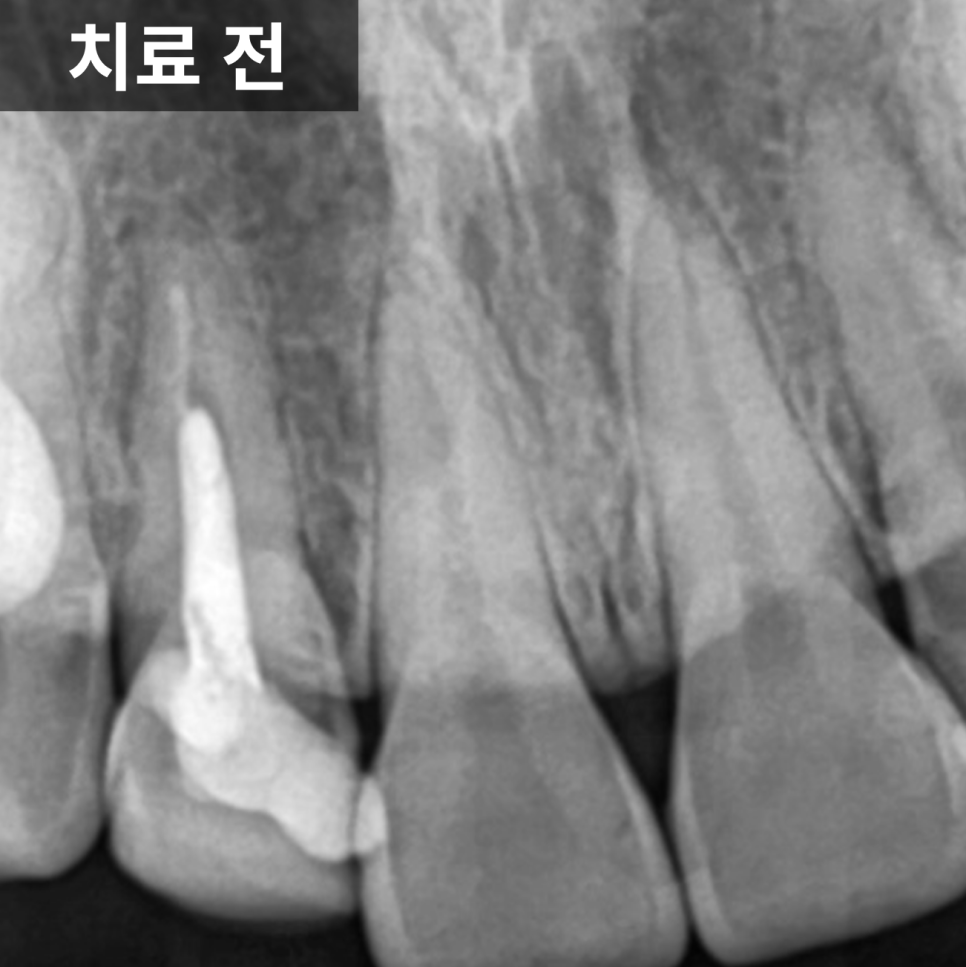

해당 치아는 왼쪽 아래 어금니였고,

잇몸에서 고름이 배출되는 통로가 형성되어 있는 상태였습니다.

엑스레이를 확인해보니

일반적인 포스트가 아니라

캐스트 포스트가 깊게 삽입되어 있었고,

주변 신경치료 상태 역시

깔끔하게 마무리된 형태는 아니었습니다.

이러한 경우에는 단순 치근단 염증뿐 아니라

치근파절 가능성을 반드시 함께 고려해야 합니다.

그 위치가 치아의 상방 쪽에 자리하고 있었고

뿌리를 따라 세로 방향으로 뼈가 녹아 있는 양상이 관찰되었습니다.

이런 형태는 일반적인 염증보다

치근파절에서 자주 보이는 패턴으로,